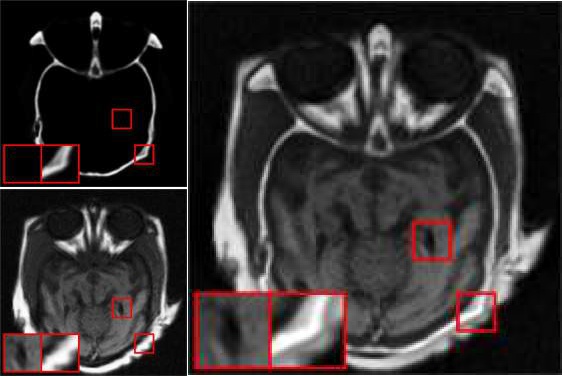

medical and determination of disease and cancers.